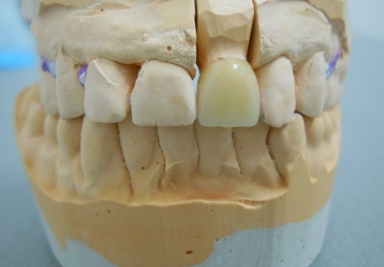

Full porcelain crowns

porcelain veneer, full porcelain crowns